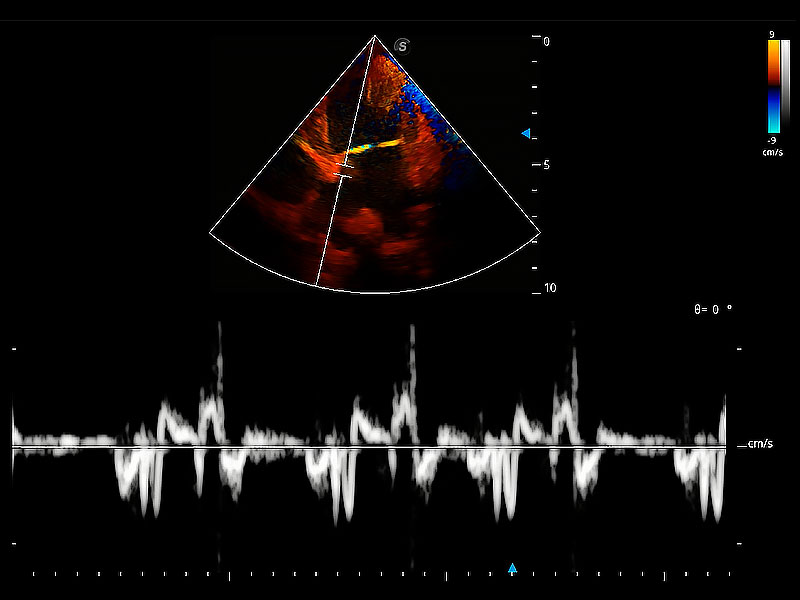

實時用顏色表示心肌組織運(yùn)動,觀察和定量組織的運(yùn)動情況,對快速檢測與評估心肌的灌注和活性、電傳導(dǎo)及心肌收縮和舒張功能等均能提供重要的診斷信息。

隨著取樣門位置改變,頻譜多普勒包絡(luò)可進(jìn)行自動眼蹤測量,且可自由配置測量的參數(shù)。